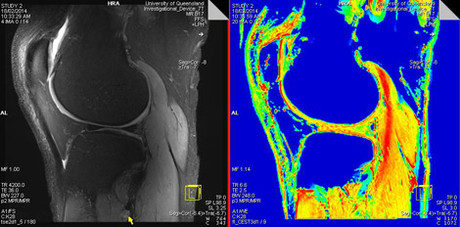

The Southern Hemisphere's most powerful body scanner, capable of capturing extremely fine anatomical details, is now operating at The University of Queensland.

UQ’s Centre for Advanced Imaging Director Professor David Reutens said the $11m 7T scanner provided unprecedented opportunities for imaging research in Australia.

Centre for Advanced Imaging Research and Technology Director Professor Ian Brereton said the Siemens Healthcare MAGNETOM 7T scanner’s ultra-high field strength could measure tissue metabolism non-invasively at a spatial resolution not previously possible.